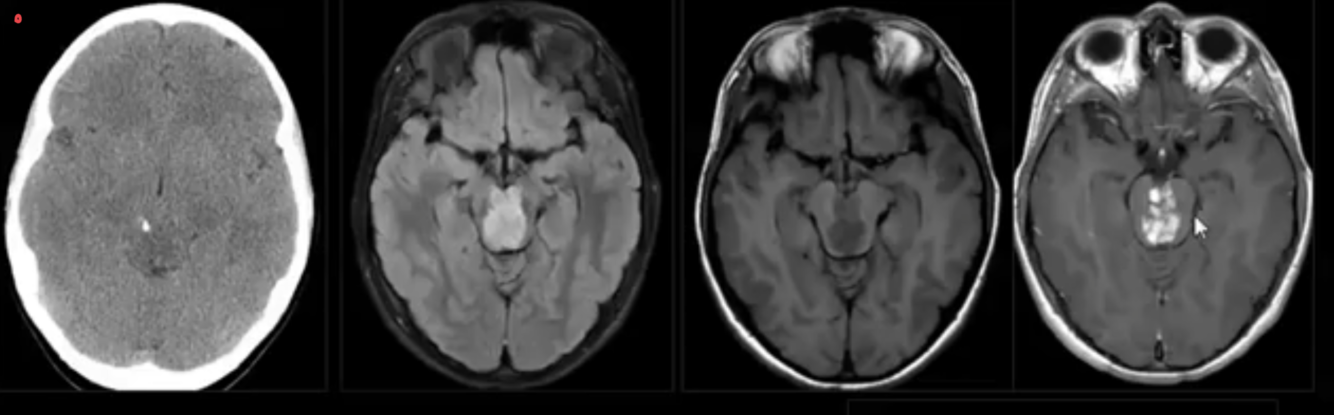

AQUEDUCTAL STENOSIS:

-acquired causes?

Extrinsic compression

tectal plate glioma / pineal tumour / posterior fossa tumour / cerebral vascular malformation